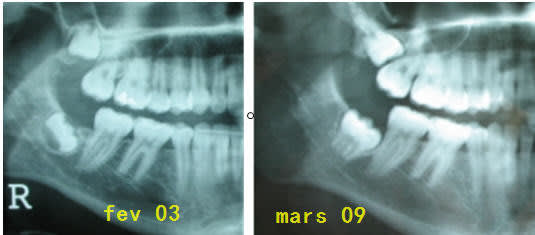

Mesialisationdessecteursposterieurs rupbvy - Eugenol

Wolford hm5yx3 - Eugenol

Le problème est qu'on manque de données sur la puissance de la force d'evolution de la DDS, comparée à la force d'ancrage du groupe latéral... Ton schéma présente une indication d'extraction, à mon sens, non pas par la force exercée mais par les risques pour la 7.